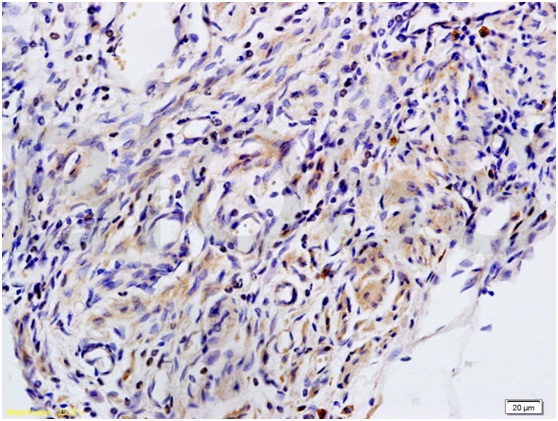

Tissue/cell: human rectal carcinoma; 4% Paraformaldehyde-fixed and paraffin-embedded; Antigen retrieval: citrate buffer ( 0.01M, pH 6.0 ), Boiling bathing for 15min; Block endogenous peroxidase by 3% Hydrogen peroxide for 30min; Blocking buffer (normal goat serum,C-0005) at 37℃ for 20 min; Incubation: Anti-MIP2/GRO Beta/CXCL2 Polyclonal Antibody, Unconjugated(bs-1162R) 1:200, overnight at 4℃, followed by conjugation to the secondary antibody(SP-0023) and DAB(C-0010) staining